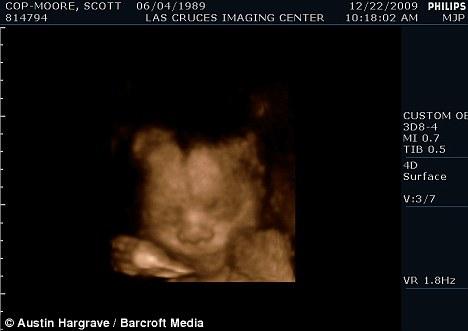

Пара транссексуалов повстречалась в 2005 году, с 2007 — решила жить вместе, а в 2008 – завести ребёнка…Что и удалось реализовать с помощью семенного материала «близкого друга», фамилия которого, по понятным причинам, не сообщается…Второй беременный мужчина, признаётся, что «невероятно счастлив» в ожидании мальчика, который должен появиться на свет в феврале…